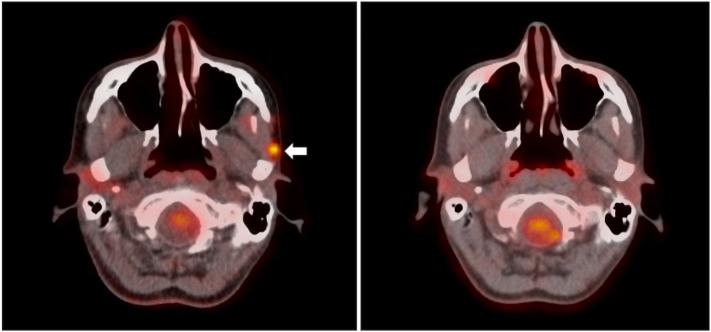

JAAD Case Rep. 2023 Oct 14;48:74-76. doi: 10.1016/j.jdcr.2023.09.039. eCollection 2024 Jun.